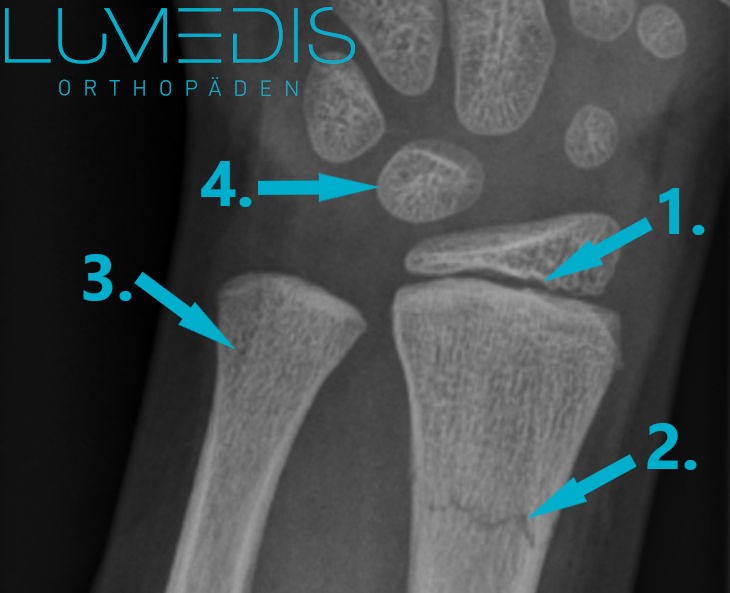

Röntgenbild eines Wulstbruchs der Speiche

Das Röntgenbild ist die wichtigste bildgebende Maßnahme zur Sicherung der Diagnose eines Handgelenksbruchs. Sie erfolgt stets in zwei Ebenen, um den Knochenbruch sicher und ohne Zweifel darstellen zu können.

Im Röntgenbild werden typische sogenannte Frakturzeichen für einen Knochenbruch sichtbar, zu denen beispielsweise die Verschiebung der Bruchstücke zueinander sowie eine Spaltbildung zwischen den Bruchstücken zählen. Auch die Unterbrechung der Knochenaußenwand zählt zu den sicheren Zeichen im Röntgenbild. Des Weiteren wird hier der sogenannte Böhler-Winkel beurteilt, der im Bereich des Speichenendes gemessen werden kann und zur Beurteilung für die weitere Behandlung eine Rolle spielt.